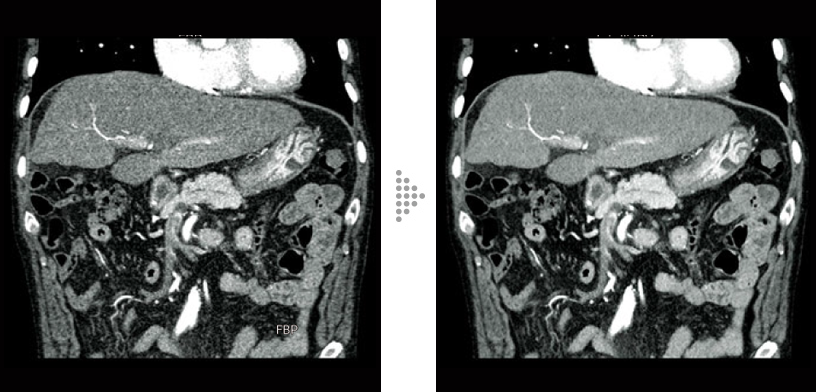

FBP(izquierda)

Intelli IPV(derecha)